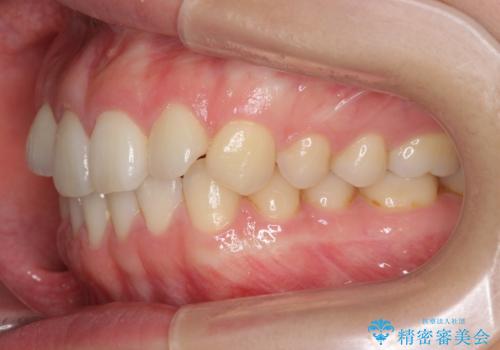

下の前歯が1本短い インビザラインと部分矯正の組み合わせ

- 前歯のガタつきと、下の前歯が一本短いことを主訴に来院。

インビザラインのマウスピースではめる装置で歯を引っ張り出すことは難しいと説明し、下の前歯だけワイヤー部分矯正を行ってからインビザライン矯正で仕上げをしました。

難しい部分を短期間ワイヤー矯正を行ってからのインビザラインは、全体治療が短くなるだけでなく、仕上がりもよくなるのでオススメです。